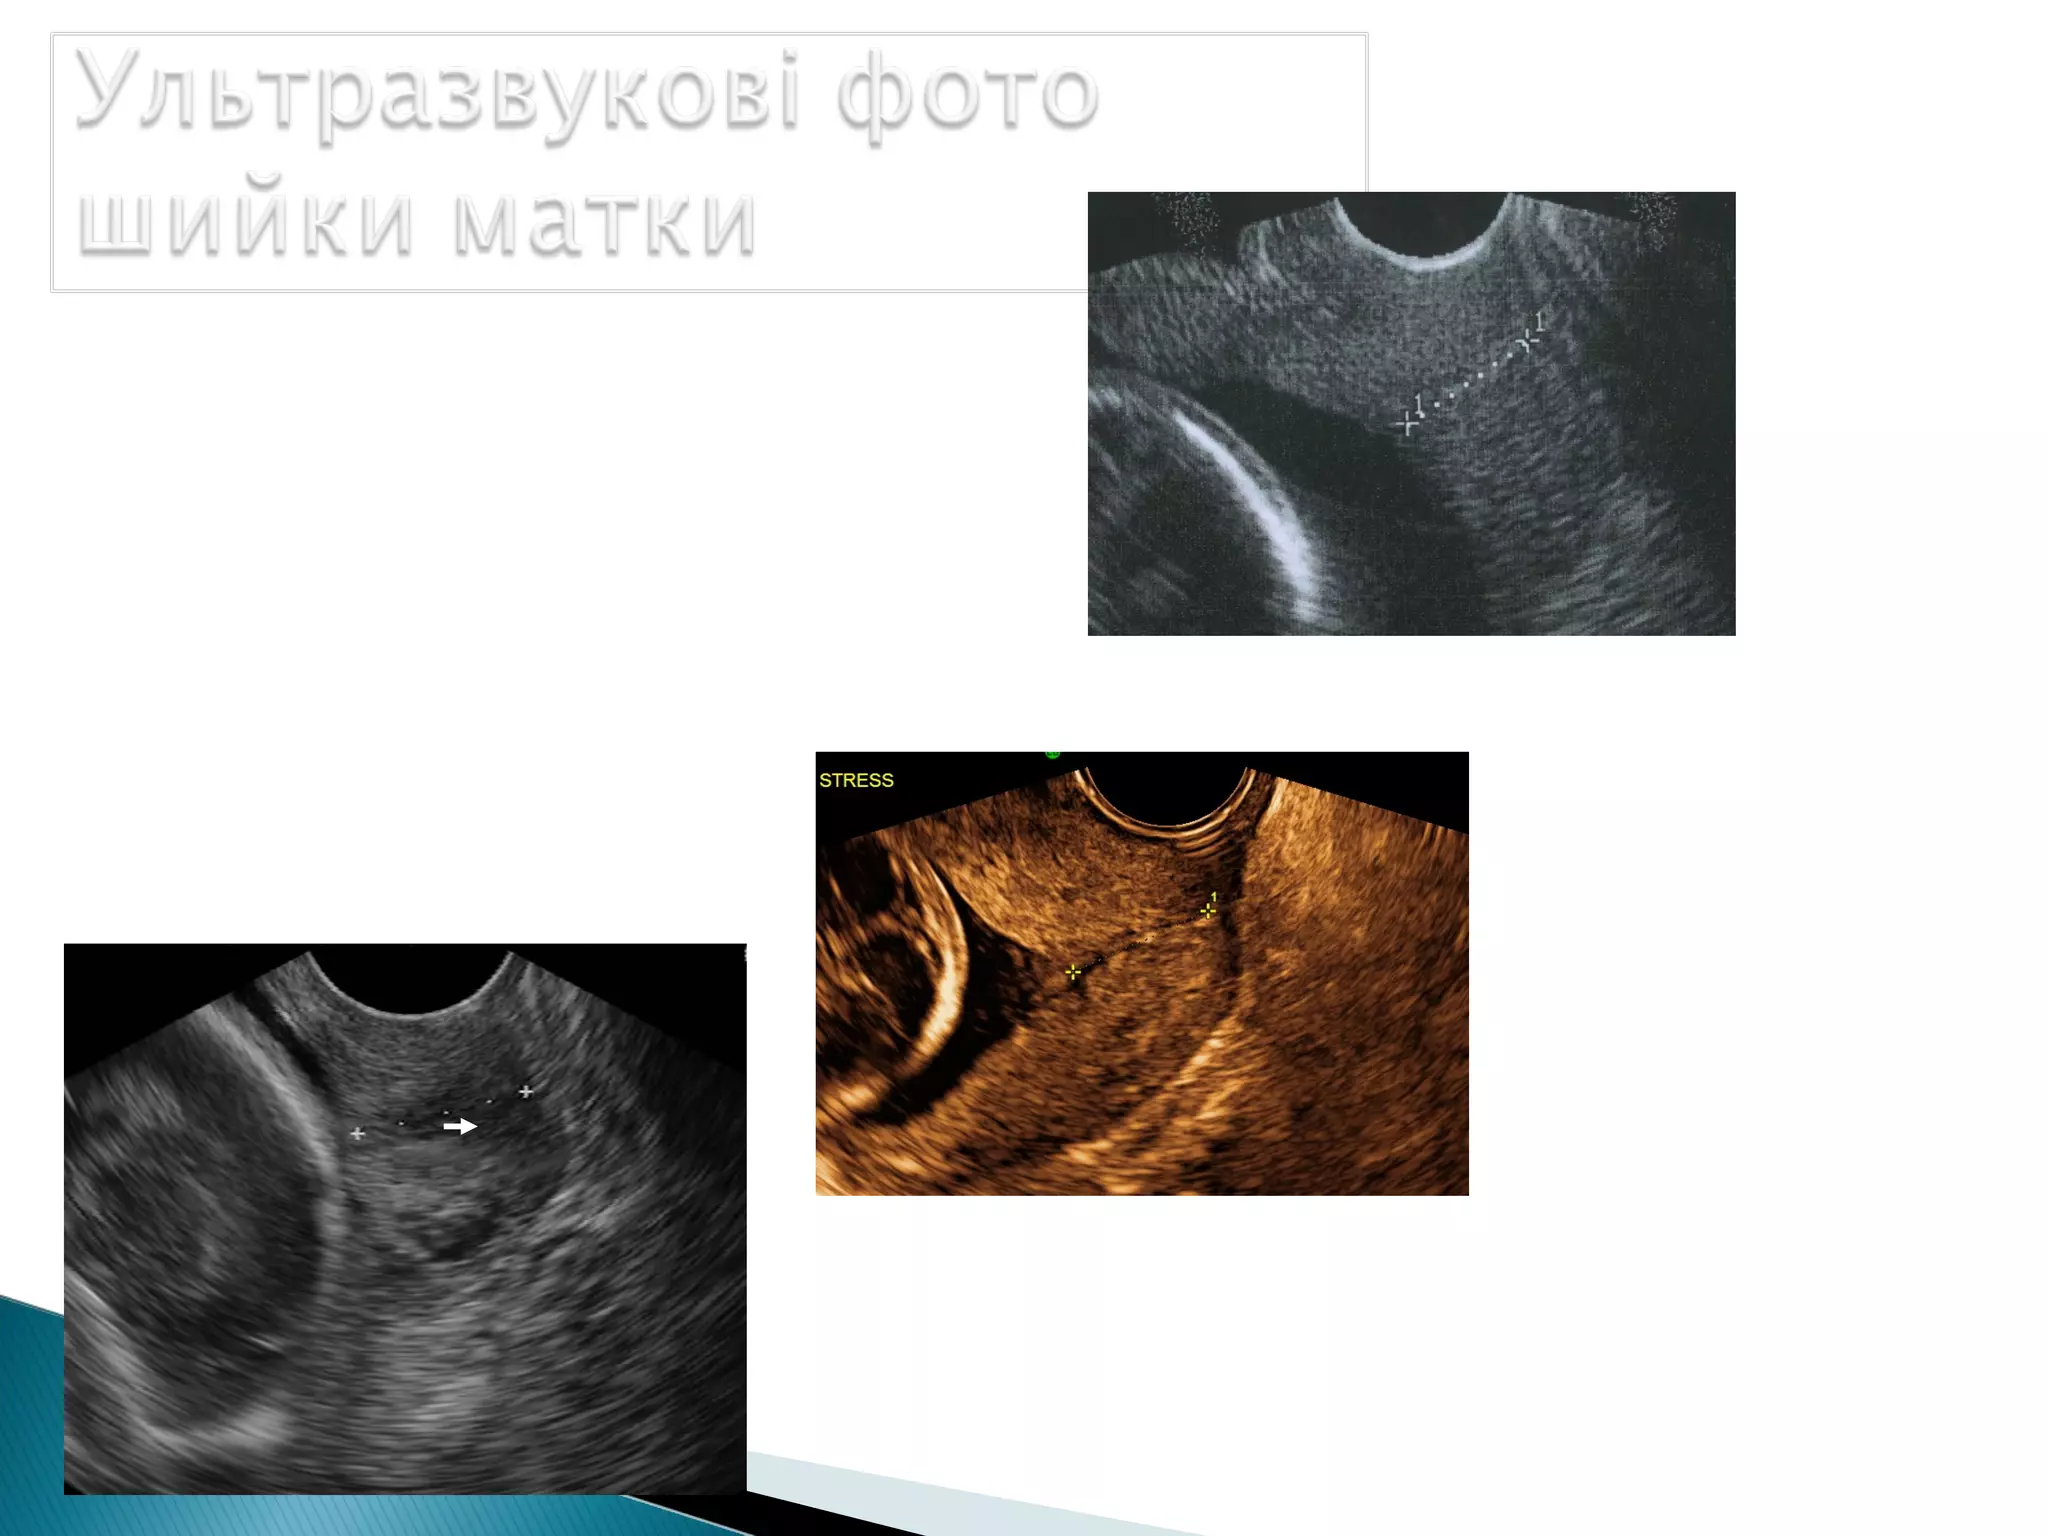

Ультразвукові зрізи шийки матки

Вимірювання довжини шийки матки

проводиться лінійно від

зовнішнього до внутрішнього вічка.

Зовнішнє вічко

Цервікальний канал

Canal Width

Внутрішнє вічко

Сечовий міхур

Хоріональна

мембрана

Після одержання повздовжнього зрізу шийки слід

досягти чіткої візуалізації ендоцервікса для визначення

внутрішнього вічка.